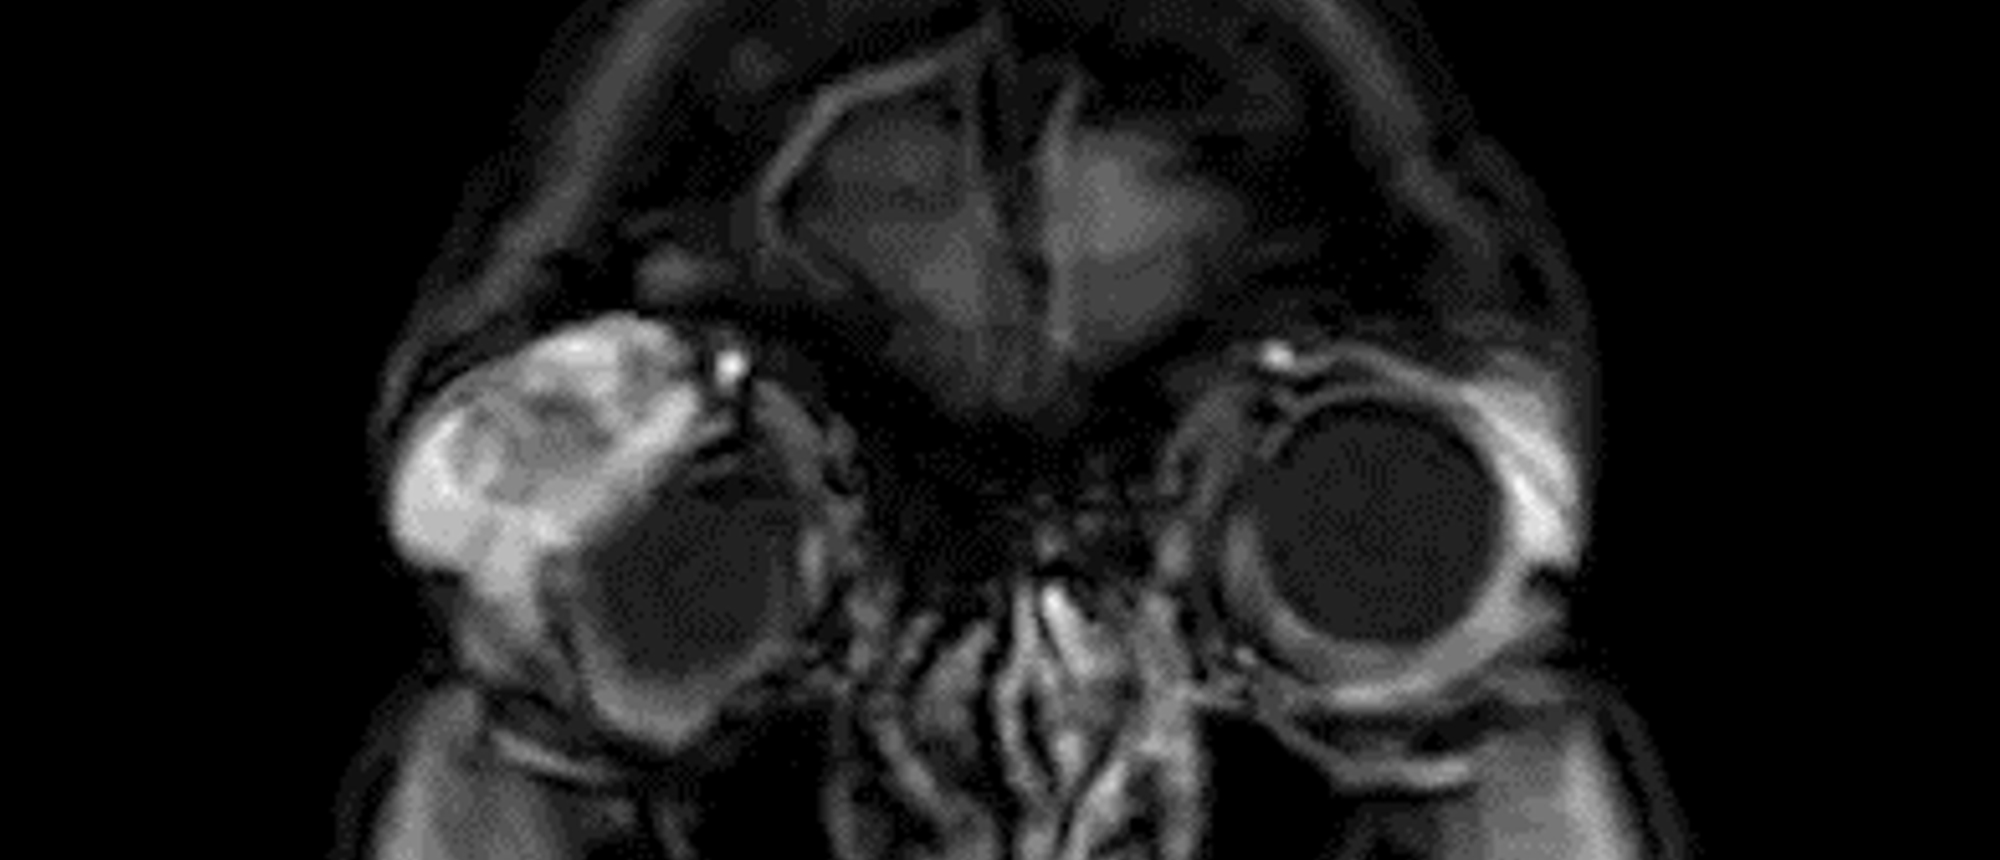

Vitamin A Induced Intracranial Hypertension A patient was found to have acute promyelocytic leukemia and was started on all-trans-retinoic acid (ATRA). He was also noted to incidentally have bilateral papilledema and MR imaging demonstrated multiple stigmata suggestive of chronically elevated intra…